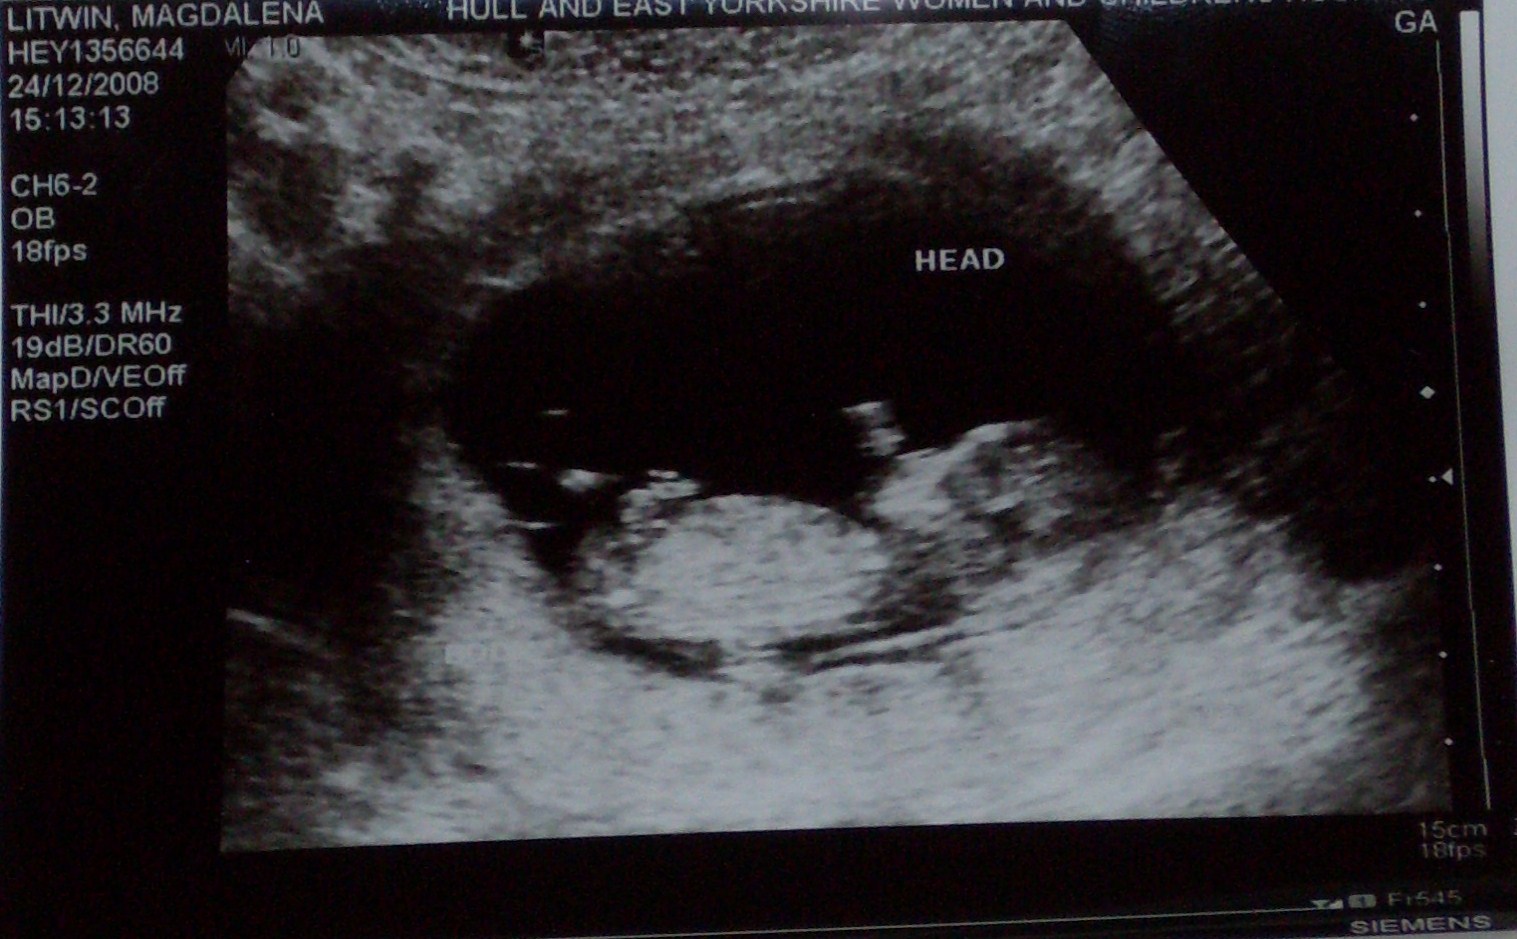

) Moj bardzo chce miec chlopaka Ohh wiecie co To jest niesamowite tak pierwszy raz zobaczyc dzidzi w brzuchu Tak uswiadomisc sobie ze to prawdziwe ze on tam naprawde jest Ohhh to ze ja ryczalam to normalne ale ze Mojemu sie lezka zakrecila w oku hihihi Teraz czekamy na pierwsze kopniecia